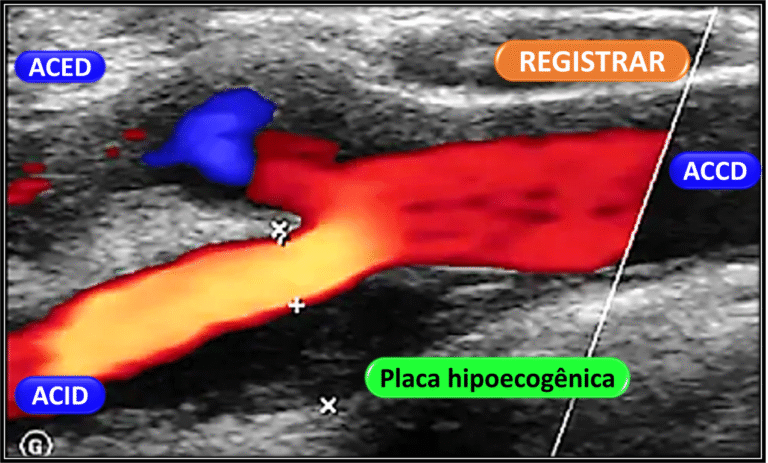

Com placa sem estenose em bifurcação carotídea

Ausência de espessamento parietal, não foram observadas tortuosidades significativas, com a presença de placas ateromatosas (hiperecogênicas, regulares e homogêneas), a maior com 2,5 mm de espessura, localizada em bifurcação, mas sem alterações de fluxo ao Doppler.